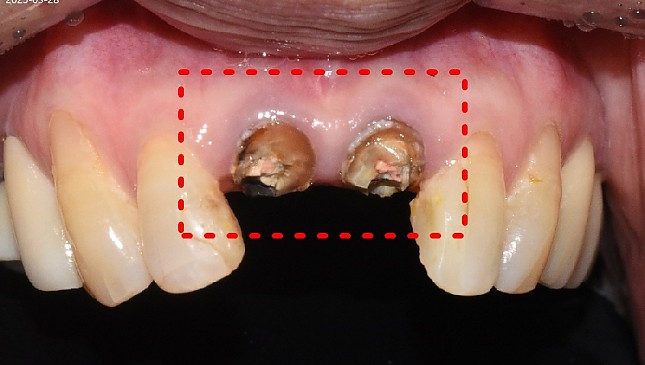

치아살리기 치료 전후 사진

잇몸재생교정 치료 전후사진

잇몸 전체가 무너져 동시다발적으로 죽어가던 치아들을 한꺼번에 살려 냅니다.